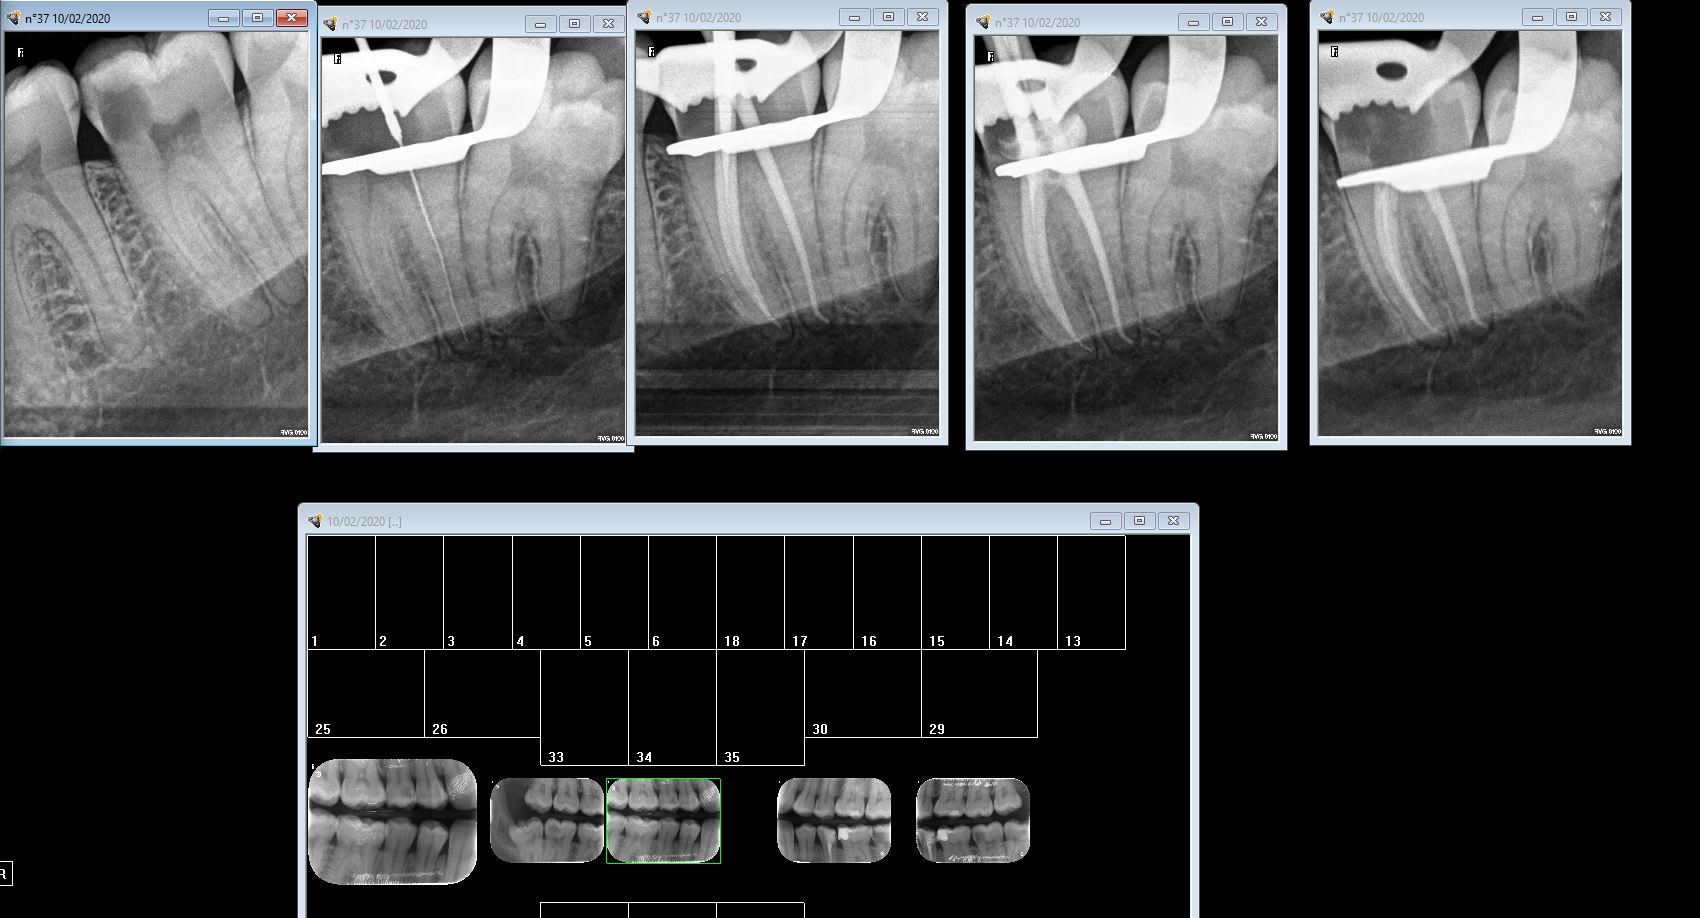

Endo 37 2 bwt978 - Eugenol

fistule 69

10/02/2020 à 21h17

Chicot...

La 6 pour le distale et la 4 pour les médiaux ?

Conicité variable chez VDW.6-4-2...

chicot29

10/02/2020 à 23h30

Je commence à 4% et finis à 6%. Faut plus de canaux traités pour avoir une impression.